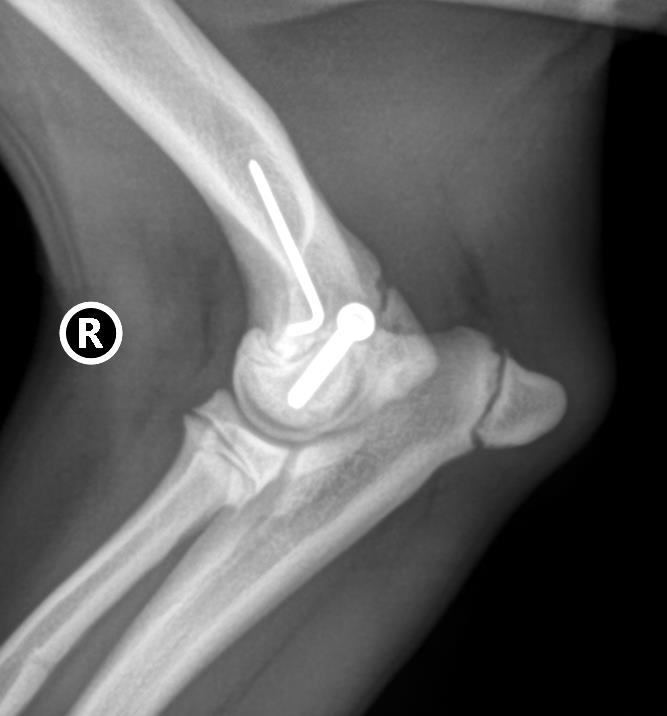

- Breites chirurgisches Spektrum innerhalb der Weichteilchirurgie, der orthopädischen Chirurgie, Neurochirurgie, Thoraxchirurgie u.a. chirurgische Fachgebiete